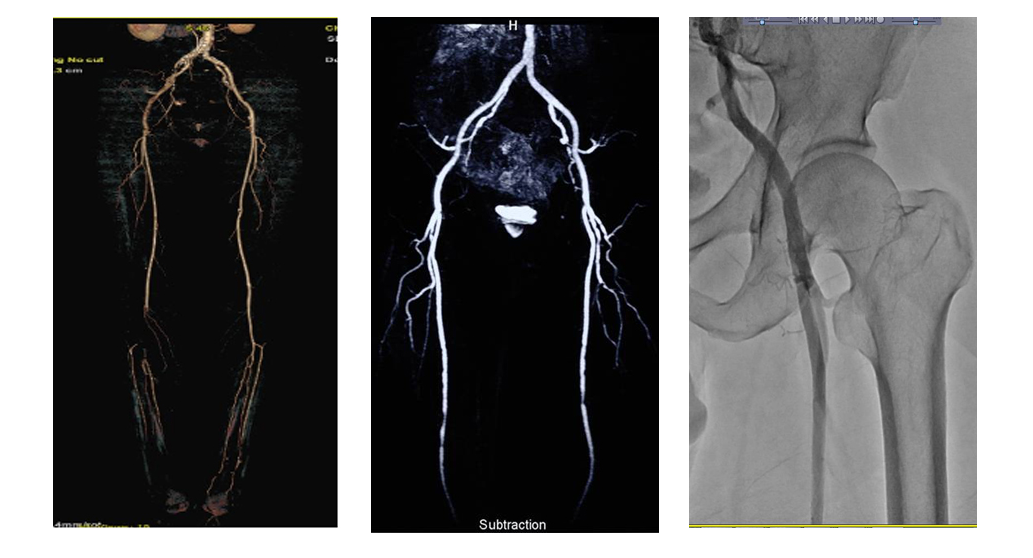

- 슬와동맥 스텐트 삽입술은 슬와동맥 협착을 치료하기 위한 비침습적인 방법입니다. 좁아진 부위에 스텐트를 삽입하여 혈관을 확장하고 혈류를 원활하게 만듭니다.

- 이 방법은 슬와동맥의 협착이 비교적 가벼운 경우에 효과적일 수 있으며, 수술 후 회복 기간이 상대적으로 짧습니다.

- 스텐트는 혈관이 좁아지는 것을 방지하고 혈류를 지속적으로 개선하는 데 도움을 줍니다.

2.3. 혈관 확장술 (Angioplasty)

- 혈관 확장술은 좁아진 동맥을 풍선을 이용하여 확장시키는 시술입니다. 풍선이 좁은 부위에 삽입되어 부풀어 올라 혈관을 넓혀 혈류를 원활하게 만듭니다.

- 이 방법은 슬와동맥 협착이 비교적 적당한 정도일 때 사용될 수 있습니다. 혈관 확장술 후에는 때때로 스텐트 삽입이 추가로 필요할 수 있습니다.